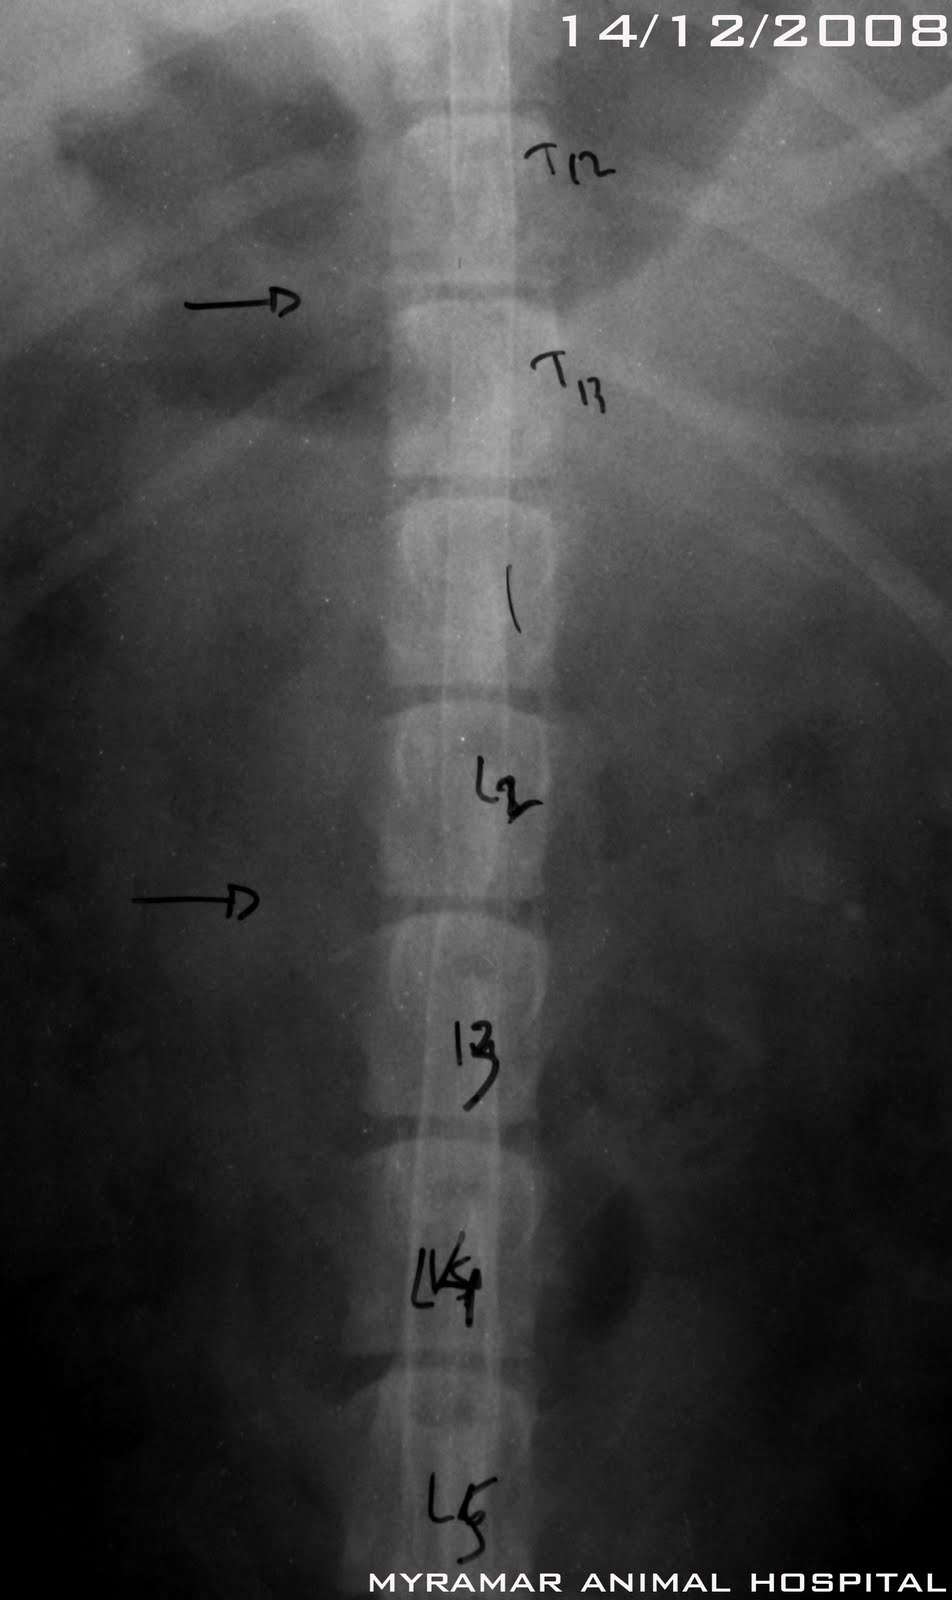

Polina, este cruce de Cocker de 8 años de edad, llega referido al hospital después de 36 horas de paraplejia.

A la exploración presenta paraparesia no ambulatoria con disminución de ambos reflejos patelares e hiperreflexia de los flexores y NO presencia de dolor profundo. La mielografía revela elevación y disminución de la columna ventral de contraste en C3-C4. Además presenta una puntual elevación en el espacio T13-L1 sin relevancia clínica.

Se presenta estudio radiológico-mielográfico del caso.